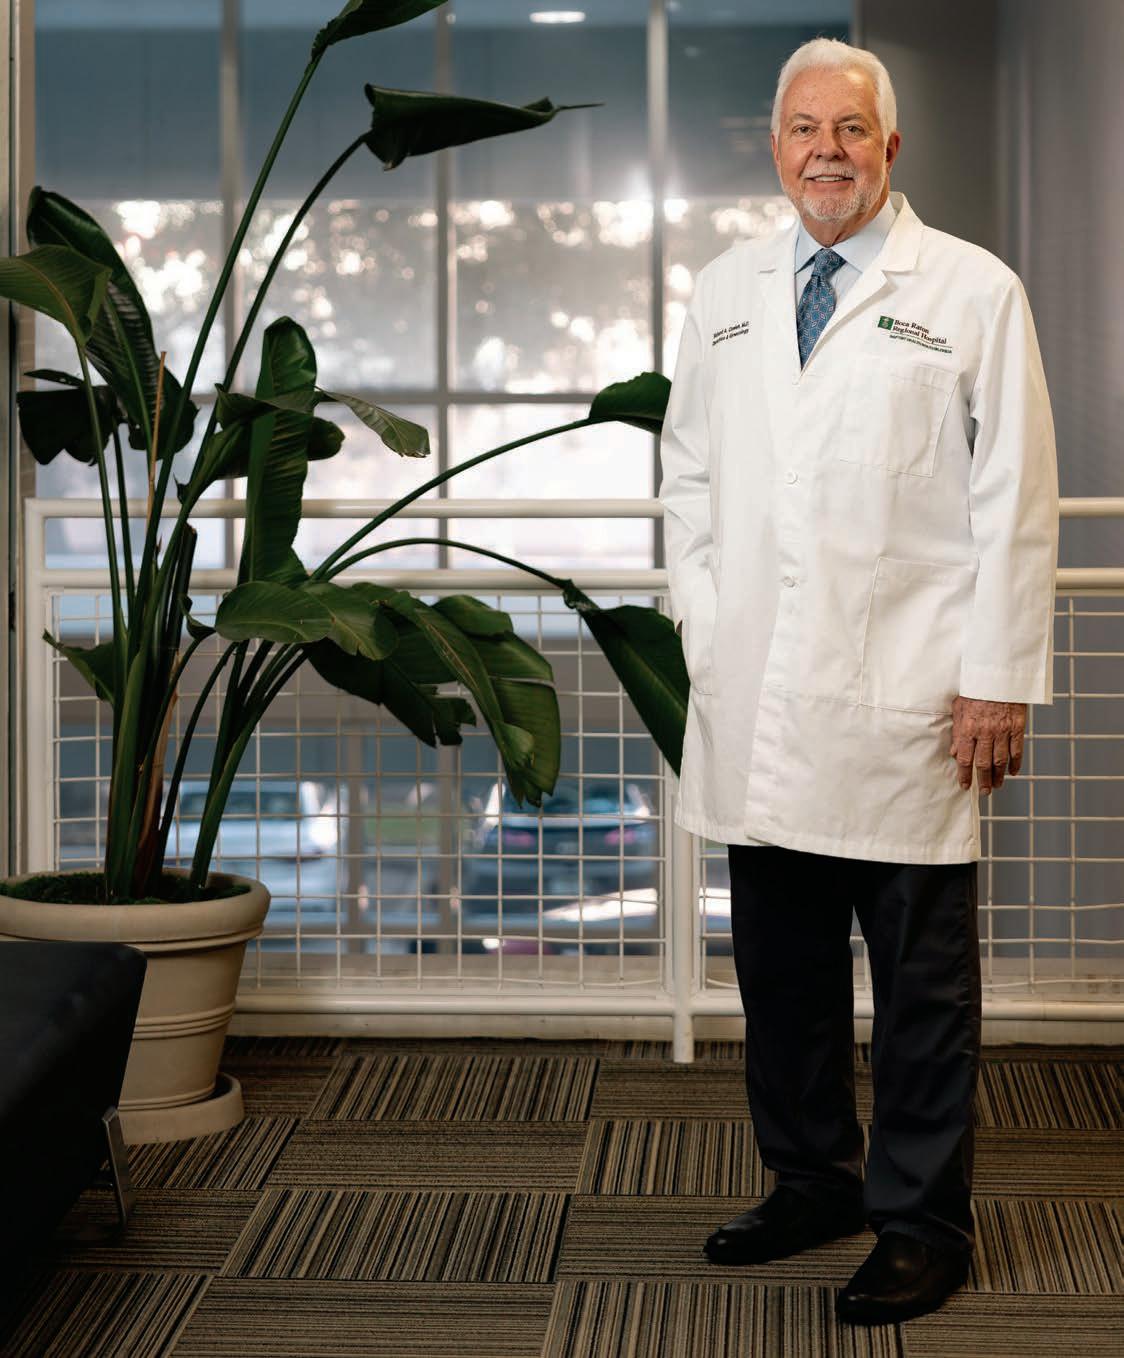

Fedele pays it forward to the next generation of nurses, earning her the Woman Volunteer of the Year

Written by CHRISTIANA LILLY

“Astate of shock”—that’s how Terry Fedele described her reaction to being named the Junior League of Boca Raton’s Woman Volunteer of the Year this past November. To be frank, she may have been the only one in the ballroom who felt that way. In her time in Boca Raton—she moved here in 2008—Fedele has become a vital resource in a community where it can be hard to stand out among all the philanthropic women. Yet she does just that, passing on her love of nursing to students.

Born and raised in Pittsburgh, Fedele lived in the Steel City until she and her husband, Jerry, moved to Boca Raton for him to take the top spot at Boca Raton Regional Hospital. She studied nursing and nursing administration at the University of Pittsburgh and then earned her master’s in public management at Carnegie Mellon. She got her start as a registered nurse in obstetrics, helping high-risk expectant mothers at UPMC Magee-Womens Hospital and seeing them through to their deliveries.“Ever since I was a young child, I always loved people and wanted to care for others, and from as long back as I can remember, I always wanted to be a nurse,” she says. Fedele then transitioned into management at some of Pittsburgh’s leading hospitals, including executive vice president of hospital operations at Suburban General Hospital.

When the couple relocated to Boca Raton, Fedele says “the community embraced us,” and it was easy for her to get involved in local causes.“I witnessed the commitment of so many individuals that devoted their time and talents to many different organizations, and that really, to me, created an impact that distinguishes Boca Raton from other communities,” she says. With her background in nursing, joining the table at Florida Atlantic University’s Christine E. Lynn College of Nursing was a natural fit. She has since served as chair of the college’s board as well as president of the Caring Hearts Auxiliary; she has also volunteered on numerous committees for Boca Regional.

During her tenure, Fedele turned the College of Nursing’s White Coat Ceremony into a fundraiser, helping raise $190,000 in scholarships to 567 students. She also planned the college’s 40th anniversary celebration as a fundraiser, bringing the school $100,000. “I had to put myself through college. My parents did not have the means, and that was one of their concerns on how I was going to [go to college],” Fedele remembers.“And so I look at the students, and I think to myself, ‘How can we help them?’” Finally, she has

helped raise $2 million through the Keep Memories Alive Walk, benefiting the Louis and Anne Green Memory and Wellness Center. Other organizations she has supported include the George Snow Scholarship Fund, the YMCA of South Palm Beach County, the Lynn Conservatory of Music and Soroptimist International.

Woman Volunteer of the Year, indeed.

ON NURSING: It’s a fabulous career. If I had to do it over, people ask me all the time, would you be a nurse again? And the resounding answer is,“Absolutely.” There’s nothing better than, at the end of the day, knowing that you positively affected someone’s life.

THE NEXT GENERATION: It is so great to sit there and watch those students walk across the stage [and] have their white coat put on them by the professors, because it brings back memories, and you never forget how special that time was for you. I look at these young nurses; they’re the ones that are going to be taking care of me as I age.

WINNING WVOY: I was in a state of shock; we could not believe it. I said to my husband,“I hope I didn’t sound like a bumbling idiot,” because I wasn’t even sure what to say. I just was truly in a state of shock. … When you look at all the nominees, truly so many remarkable women to me, I accept the award on behalf of all of them, because everyone is so deserving, and I think that’s why I was so shocked, because I didn’t see myself as any more deserving than anybody else.

LEARNING VOLUNTEERISM: I look at my parents, and they were always,“you pitch in, you do whatever it is that needs to be done. You be helpful, and you care about your community. You want to be a good member of the community.” I’ll credit them.

Millions of Americans have vascular disease, which can range from varicose veins and debilitating circulation problems in the legs to bulging arteries in other parts of the body. If you’ve been diagnosed with a condition that a ects your blood flow, getting expert care is crucial.

At Christine E. Lynn Heart & Vascular Institute at Boca Raton Regional Hospital, a dedicated group of board-certified vascular surgeons who treat only vascular diseases work together to design the best possible treatment plan for each individual.

“Our field is broad, taking care of patients who have all sorts of problems related to their circulation,” says vascular surgeon John Motta, M.D. “We work closely with primary care doctors, cardiologists and other subspecialists to help patients manage what can sometimes be very simple things, and other times be very complicated conditions.”

When diagnosed with a vascular problem, patients should evaluate all their treatment options by asking questions about alternatives.

“It is critically important to select a surgeon and a hospital that handle a high volume of these cases,” advises W. Anthony Lee, M.D., chief of vascular surgery at Boca Raton Regional Hospital. The Institute’s comprehensive, multidisciplinary vascular program takes a team approach to elevate care.

For example, Dr. Lee and his team have fine-tuned every aspect of the surgery to repair aortic aneurysms with a clinical pathway designed to consistently provide the highest-quality, evidence-based care. This protocol has been hugely successful, shortening hospital stays and reducing surgical complications.

Dr. Lee is also working to improve care through clinical research for endovascular thoracoabdominal repair and endovascular aortic arch repair. “When we see someone for an initial consultation, we

uniquely tailor the therapy to that individual, taking into account all the latest surgical, minimally invasive endovascular and medical options available, including both FDA-approved and investigational treatments,” Dr. Lee says.

The vascular team with the Institute’s Vein Clinic provides comprehensive treatments that are both therapeutic and cosmetic to address varicose veins and other symptoms of venous disease. Varicose veins are not always a cosmetic problem; they may signal potentially serious health issues.

“We look at the entire circulatory system,” explains Eileen de Grandis, M.D., medical director of the Vein Clinic. “We look for venous disease. We look for arterial disease. We look for lymphatic disease. We get you the right diagnosis, and then recommend the optimal treatment for that specific problem.”

About half of those who consult with Dr. de Grandis’s team for varicose veins are diagnosed with other underlying health issues, she says.

“Treating the medical problem can prevent or improve the cosmetic problem,” she says. “Unlike other centers, if the problem is more than cosmetic, we can address that. As a comprehensive vascular center, we treat the circulatory system as a whole.”

To learn more, visit BaptistHealth.net/ VascularSurgery or call 833-816-2328 .